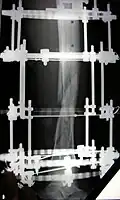

The photographs and radiographs illustrate the application and emplacement of an external fixator, an Ilizarov apparatus, to repair the open fracture of the lower left leg of a man. The photographs were taken four weeks after the patient fractured the shinbone (tibia) and the calfbone (fibula) of his left leg, and two weeks after the surgical emplacement of the Ilizarov apparatus to immobilise the leg and isolate the wound and fracture site to facilitate healing.

X-ray of the fracture site and the emplaced apparatus, two months post-fracture; perspective 1-4.

X-ray of the fracture site and the emplaced apparatus, two months post-fracture; perspective 2-4.

X-ray of the callus forming at the fracture site, three months post-fracture; perspective 3-4.

X-ray of the callus forming around the fracture site, three months post-fracture; perspective 4-4.

X-ray perspectives of the callus-formation progress and healing of the fractured tibia and fibula bones, four months post-fracture.